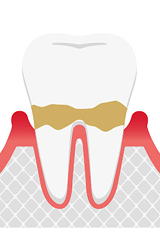

歯肉炎

歯肉炎とは、歯肉溝と言われる歯と歯茎の隙間に磨き残しや汚れが溜まり、細菌が繁殖することで周囲の歯茎が炎症を起こし腫れてしまうことで、ブラッシング時の出血や自然出血が起こる状態を示します。

汚れがこびりついて固まってきますと歯石になります。歯石になってこびりつくと、慢性的に周囲の歯茎が腫れやすくなります。歯肉炎の段階では歯石取りやTBI(歯ブラシ改善)、フロスなどを使用することで改善されます。

軽度歯周炎

歯肉炎が進行して悪化してくると、歯周炎という状態になります。

腫れている歯茎が、深い部分に少し進行した状態です。歯を支えている周辺組織が壊されていく初期段階となります。歯根膜、歯槽骨など歯を支えている組織が歯周病菌の侵入を防ごうとする自己防衛の免疫により破壊されていきます。軽度歯周炎と歯肉炎は、見た目の病態は同じです。

歯肉溝が深くなると歯周ポケットと呼び名が変わります。通常1〜2mmの溝が3〜4mmと少し深くなってくることが特徴です。プロービングといわれる歯周病検査をしないと歯肉炎か歯周炎か判別は難しいです。初期段階であれば、破壊された組織も元に戻る場合もあります。